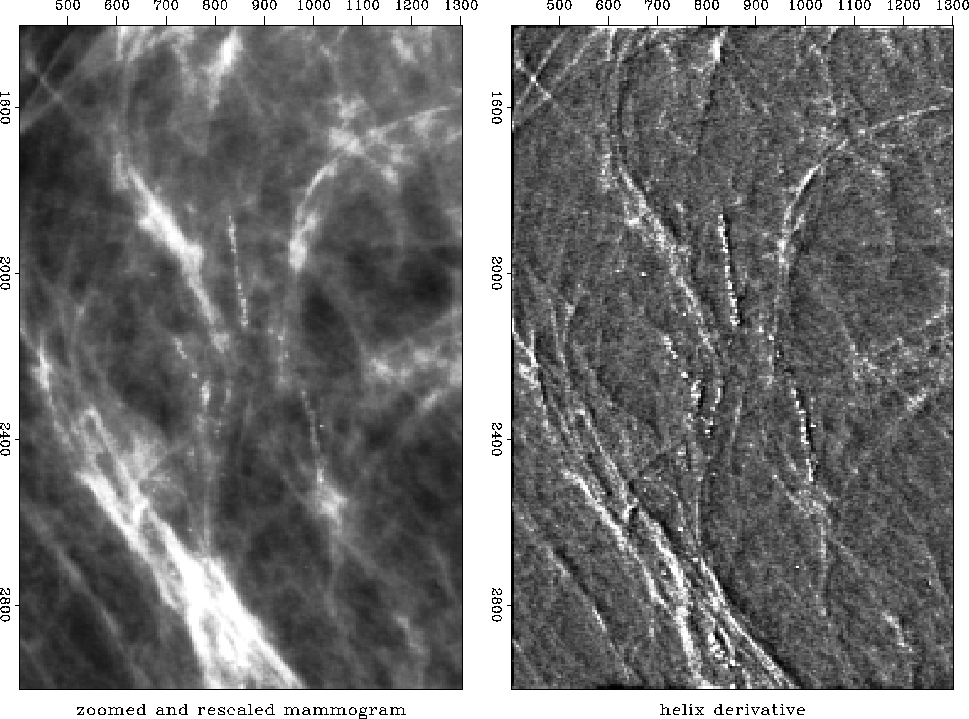

Mammogram (medical X-ray). The cancer is the ``spoked wheel.'' (I apologize for the inability of paper publishing technology to exhibit a clear grey image.) The white circles are metal foil used for navigation. The little halo around a circle exhibits the impulse response of the helix derivative.

First I had a problem preparing Figure [*]. It shows shows the application of the helix derivative to a medical X-ray. The problem was that the original X-ray was all positive values of brightness so there was a massive amount of spatial low frequency present. Obviously an x-derivative or a y-derivative would eliminate the low frequency, but the helix derivative did not. This unpleasant surprise arises because the filter in equation (11) was truncated after a finite number of terms. Adding up the terms actually displayed in equation (11), they sum to .183 whereas theoretically the sum of all the terms should be zero. From the ratio of .183/1.791 we can say that the filter pushes zero frequency amplitude 90% of the way to zero value. When the image contains very much zero frequency amplitude, this is not good enough. Better results could be obtained with more coefficients, and I did use more coefficients, but simply removing the mean saved me from needing a costly number of filter coefficients.

A final word about the doctor. As she was about to leave my office she suddenly asked whether I had scratched one of her X-rays. We were looking at the helix derivative and it did seem to show a big scratch. What should have been a line was broken into a string of dots. I apologized in advance and handed her the original film negatives which she proceeded to inspect. ``Oh,'' she said, ``Bad news. There are calcification nodules along the ducts.'' So the scratch was not a scratch, but an important detail that had not been noticed on the original X-ray.

In preparing an illustration for here, I learned one more lesson. The scratch was small, so I enlarged a small portion of the mammogram for display. The very process of selecting a small portion followed by scaling the amplitude between maximum and minimum darkness of printer ink had the effect enhancing the visibility of the scratch on the mammogram itself. Now Figure [*] shows it to be perhaps even clearer than on the helix derivative.